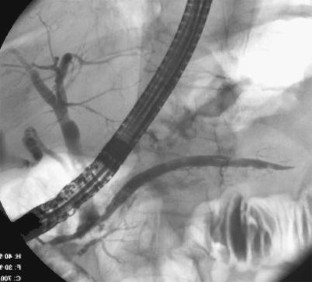

Bei einer 63-jährigen Patientin mit o. g. Risikofaktoren, einem Pancreas divisum und vermeintlichem zystischen Pankreasschwanztumor, der sich als Pseudozyste bei einer Pankreatitis herausstellte, erfolgte eine 2-jährige Behandlung rezidivierender Pankreatitisschübe. Erst bei der Behandlung eines komplizierenden Leberabszesses fiel in einer CT eine malignitätssuspekte, zum Aufstau des Pankreashauptganges führende Pankreaskopfraumforderung auf. Retrospektiv waren Gangveränderungen schon auf Voraufnahmen sichtbar. Die partielle Duodenopankreatektomie bestätigte das Pankreaskopfkarzinom.

A 63-year-old female patient with suspected cystadenocarcinoma of the pancreas tail, which was resolved as a pancreatic pseudocyst, was treated for recurrent pancreatitis for 2 years. A tumor in the pancreas head was only detected on a follow-up CT after resection of a complicating liver abscess. In retrospect, progressive pancreatic duct anomalies were visible on previous scans. Partial duodenopancreatectomy confirmed the presence of a pancreas head carcinoma.